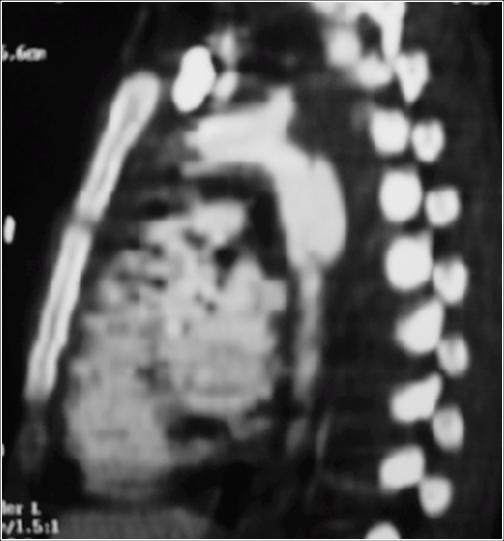

A CT Scan was ordered preoperatory:

Endovascular Procedure